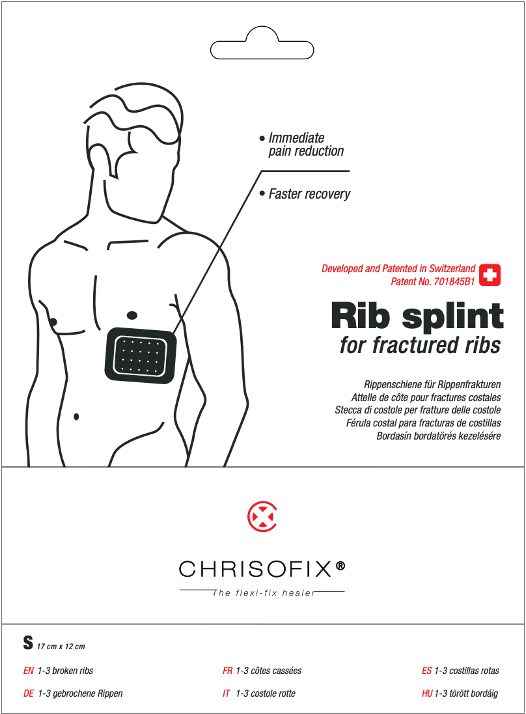

Externe mechanische Stabilisierung

Die externe mechanische Stabilisierung stellt einen bahnbrechenden Ansatz in der Versorgung von Rippenfrakturen dar und bietet eine nicht-invasive Lösung, die die Genesung des Patienten verbessert. Durch die Anwendung von gezieltem Druck minimiert diese Methode effektiv die Rippenbewegung, reduziert Schmerzen und fördert eine schnellere Heilung. Das innovative Design sorgt für Komfort und Benutzerfreundlichkeit und macht es zur bevorzugten Wahl für Patienten und medizinische Fachkräfte gleichermaßen.

Im Gegensatz zu herkömmlichen zirkulären Gürteln, die die Brustkorbausdehnung einschränken, unterstützt das lokalisierte Design der Chrisofix® Rippenbandage die natürliche Atemmechanik. Durch die Stabilisierung der Brustwand, ohne diese zu umschließen, erleichtert das Produkt tieferes Atmen und effektiveres Husten. Diese Verbesserung der Belüftung ist essenziell für die Aufrechterhaltung der Lungenhygiene und die beschleunigte Mobilisierung des Patienten.